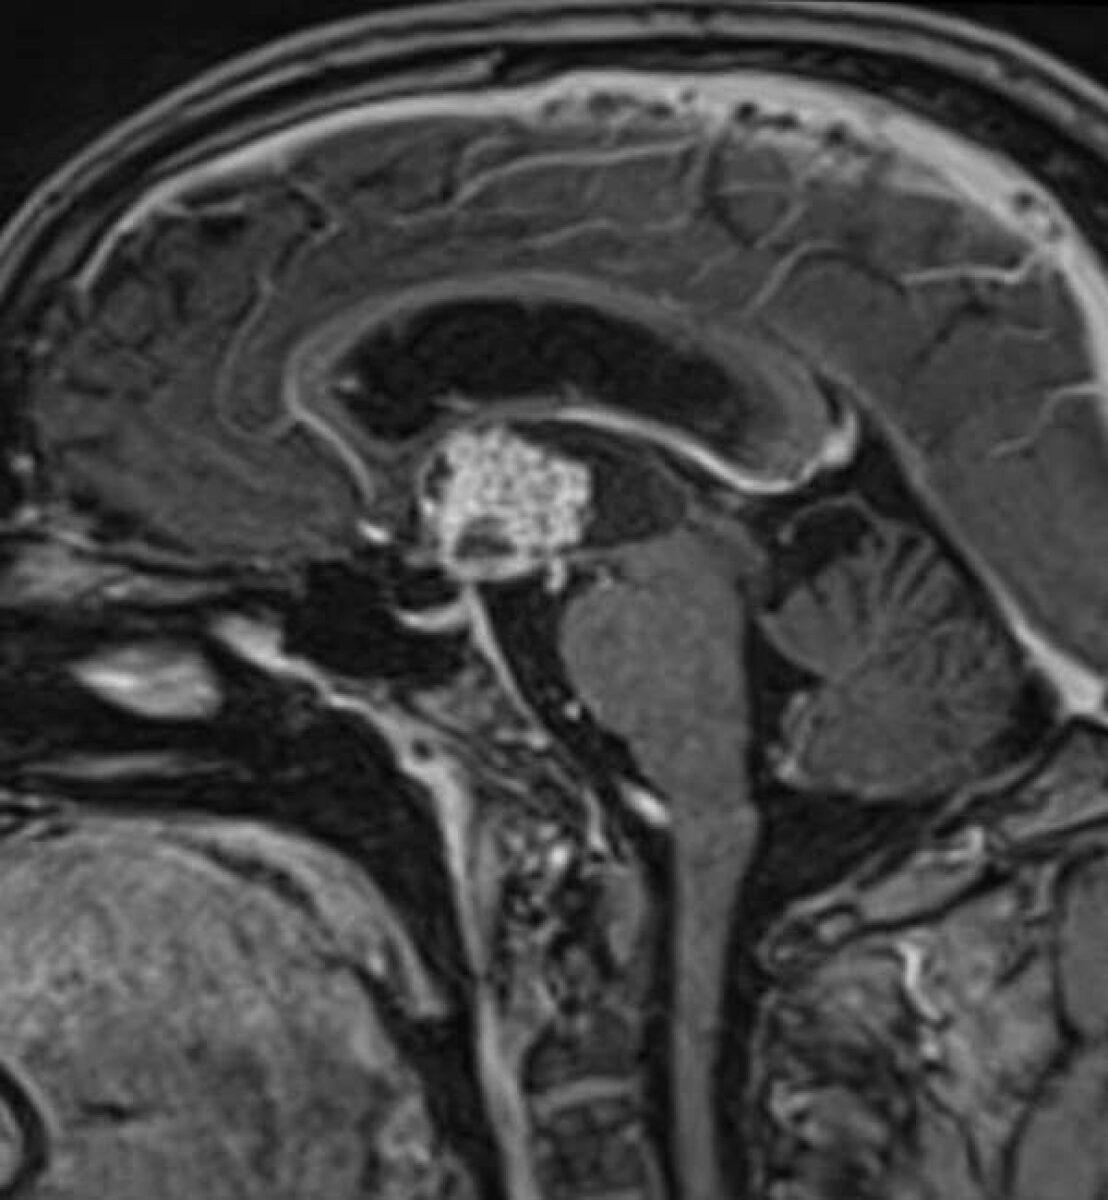

Πρόκειται περί όγκου που αναπτύσσεται στην περιοχή της υπόφυσης, της υπερεφιππιακής δεξαμενής (χώρος γεμάτος με

εγκεφαλονωτιαίο υγρό στον οποίο βρίσκονται το οπτικό χίασμα, ο μίσχος της υπόφυσης καθώς και αγγεία του εγκεφάλου), του υποθαλάμου και της 3ης κοιλίας του εγκεφάλου. Παρουσιάζεται συνήθως σε παιδιά ή νέους ενήλικες και αντιπροσωπεύει περίπου το 10% του συνόλου των όγκων του εγκεφάλου σε νέους. Μπορεί ωστόσο να διαγνωσθεί σε οποιαδήποτε ηλικία.

Το κρανιοφαρυγγίωμα είναι καλοήθης όγκος. Αναπτύσσεται όμως σε μία ιδιαίτερα ευαίσθητη περιοχή του εγκεφάλου και σχεδόν πάντα περιβρογχίζει τις ανατομικές δομές ή/και διηθεί τον εγκεφαλικό ιστό. Αναπτύσσει αποτιτανώσεις (επασβεστώσεις) καθώς και ιδιαίτερα ευμεγέθεις κύστεις, που καθιστούν πολλές φορές τη θεραπεία ιδιαίτερα δύσκολη.

Κρανιοφαρυγγίωμα